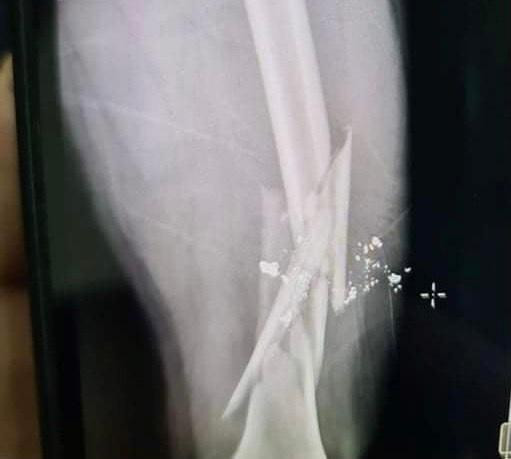

| Phần đùi nạn nhân bị gãy sau khi bị Hoà dùng súng bắn. |

Trong quá trình ngồi nhậu giữa Hoà và anh G. xảy ra mâu thuẫn dẫn đến xô xát. Do quá bức xúc, Phan Công Hoà đã dùng súng thể thao bắn anh G., khiến nạn nhân bị gãy xương đùi phải nhập viện cấp cứu.